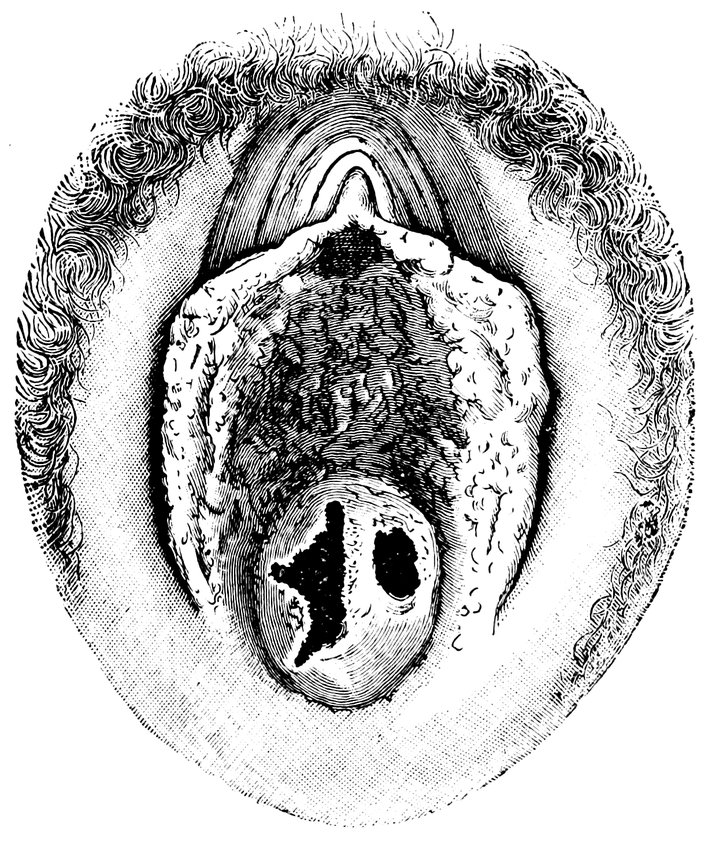

| 66. | 326 | |

| 67. | Lipoma of the Right labium majus, including the Vaginal Inlet | 328 |

| 68. | “Hottentot Apron” in an adult Woman, hanging down between the thighs (after Zweifel) | 329 |

| 69. | Elephantiasis of the Labia Majora | 330 |

| 70. | Congenital Atrophy of the Uterus (after Virchow), oi, Ostium internum; oe, Ostium externum | 500 |

| 71. | 500 | |

| 72. | Normal Shape of the Portio Vaginalis | 503 |

| 73. | Conoidal Shape of the Portio Vaginalis | 503 |

| 74. | “Apron-Shaped” Vaginal Portion, a. Greatly elongated anterior lip; b. Shorter posterior lip of the cervix | 504 |

| 75. | “Beak-Shaped” Vaginal Portion. Posterior aspect | 504 |

| 76. | Simple Hypertrophy of the Portio Vaginalis, which projected from the Vulva | 506 |

| 77. | Elongated Cervix, bent upwards | 506 |

| 78. | Cervical Polypus, originating from an Ovulum Nabothi | 510 |

| 79. | Ectropium in a Case of Bilateral Laceration of the Cervix (after A. Martin) | 514 |